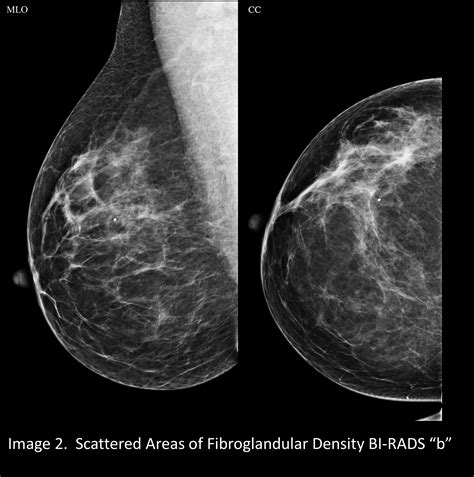

To understand why advanced imaging is necessary, it helps to know what “density” actually refers to. Breast tissue is composed of two primary types: fibrous and glandular tissue (which are dense) and fatty tissue (which is non-dense). When a radiologist looks at a mammogram, fatty tissue appears dark or transparent, while dense tissue appears solid white.

The challenge arises because breast cancer also appears as a white area on a standard mammogram. If a woman has dense breasts, the white dense tissue can essentially “mask” or hide a potential tumor, making it significantly harder to detect abnormalities. This is where the shift toward more sophisticated technology is vital.

For decades, standard 2D digital mammography was the gold standard. However, 2D images take a flattened view of the entire breast, which can lead to overlapping tissues that look like suspicious spots. A Dense Breasts 3D Mammogram, clinically known as digital breast tomosynthesis, works differently by taking multiple images from various angles. These images are then reconstructed into a series of thin “slices,” allowing the radiologist to scroll through the breast tissue layer by layer.

The interpretation of a Dense Breasts 3D Mammogram requires specialized training. Radiologists must analyze hundreds of individual slices to ensure no subtle changes are missed. By utilizing the 3D data, they can isolate specific areas of concern that might have been buried under dense, fibroglandular tissue in a 2D scan. This technological precision empowers medical professionals to provide more confident assessments, ultimately leading to better peace of mind for the patient.